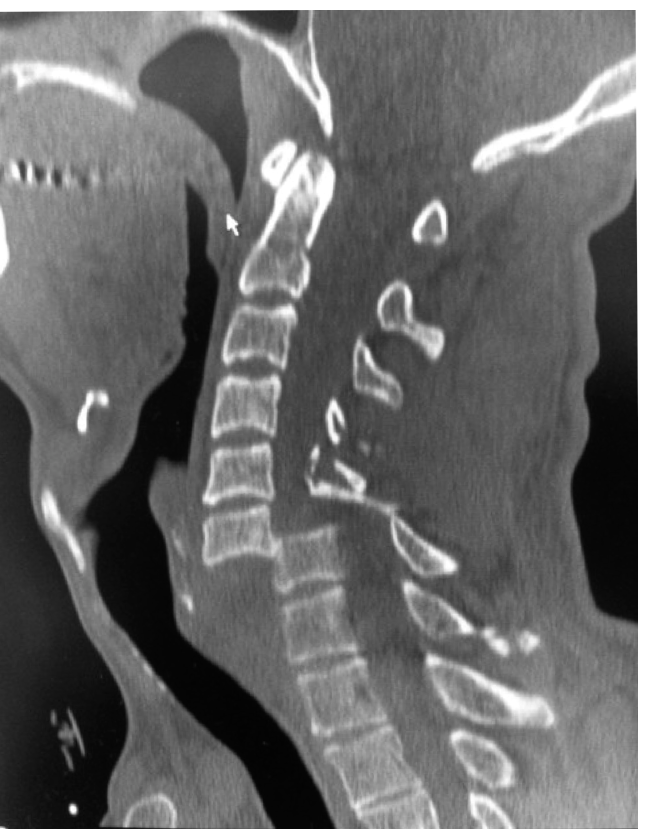

A 44-year-old man has jumped from the fifth floor of a building and has been brought to the emergency departm…